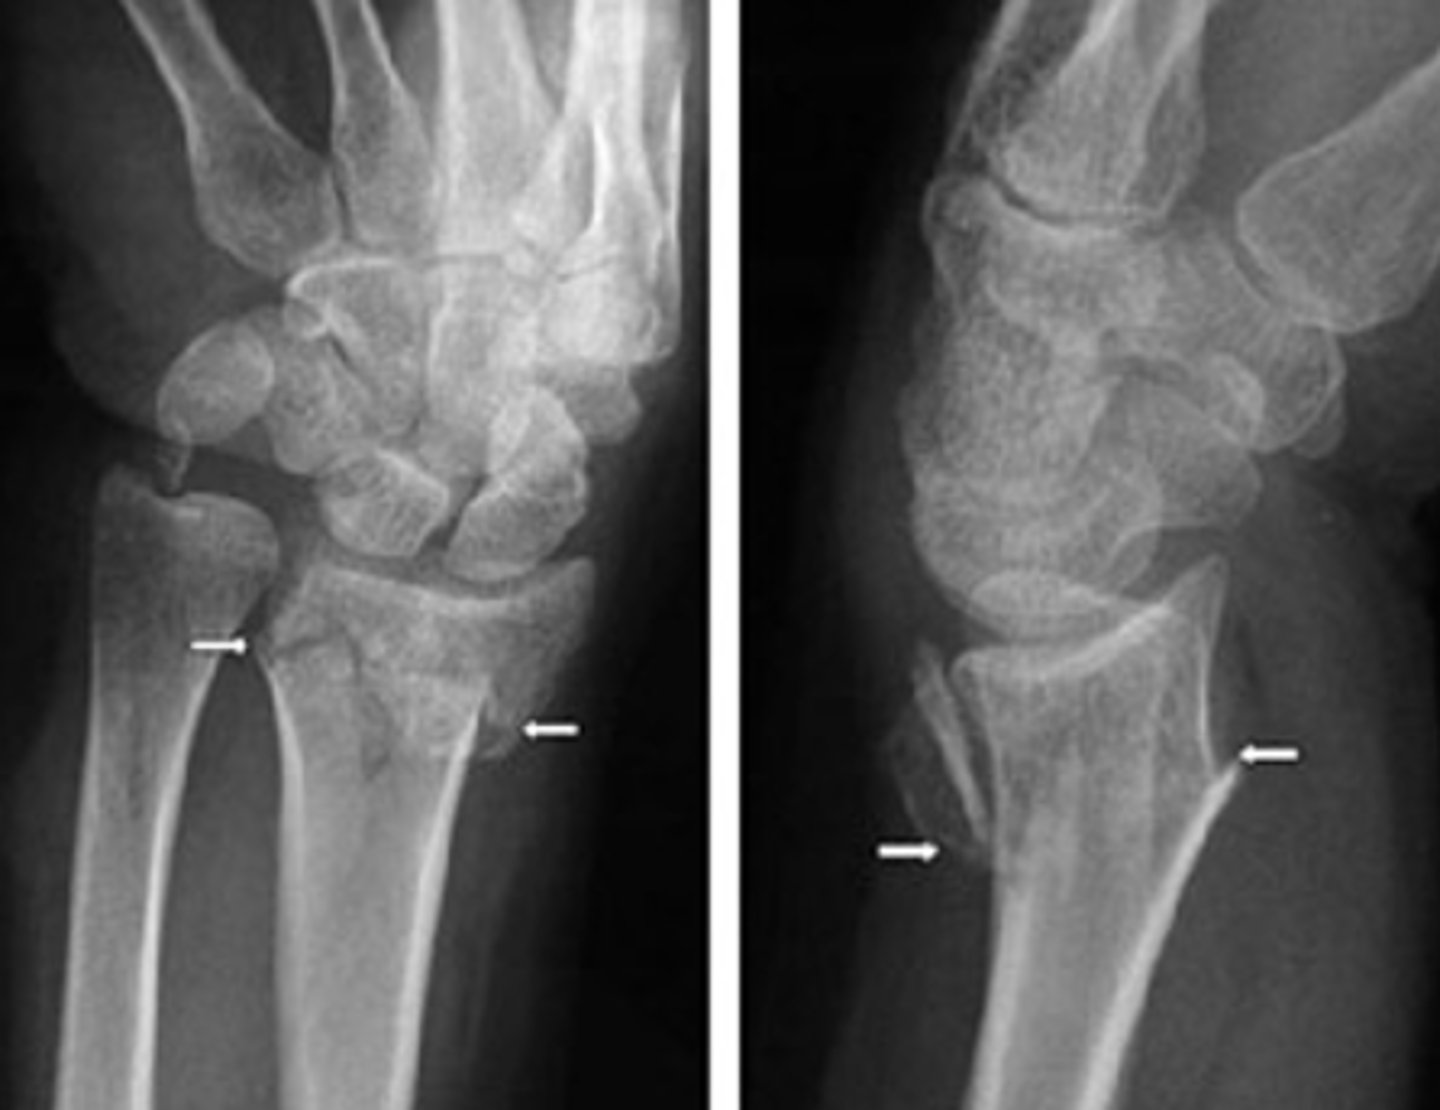

Whats happening in this one?

Answer

-This is a colles fracture.

-The comminuted fx is dorsally and radially displaced

-With volar angulation

-Extension into the joint (intra articular)

Dorsal vs volar

-Dorsal: non palm side

-Volar: palm side